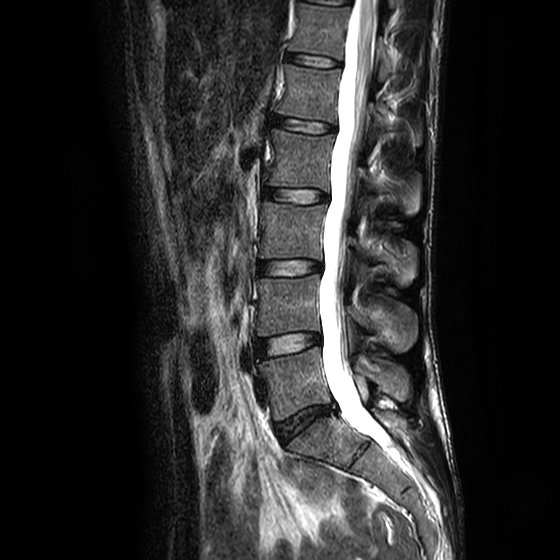

Ich bin 61 Jahre alt und arbeite als Schiffskochbin kräftig gebaut. Im August 2010 wurde ichnach einem Bandscheibenvorfall mit Wirbelgleiten im Bereich L5 -S 1 versteift. Daher kann es zu einer Reizung bzw.

Verhalten bei einer Verstei- fung der Lendenwirbelsäule Klinik für Neurochirurgie Zentrum für Ergo- und Physiotherapie Hinweise für das Verhalten nach Versteifungsoperationen. Die dorsal-dynamische Instrumentierung kann bei bestimmten Krankheitsbildern eine Alternative zur Versteifung darstellen. Die dorsal dynamische Instrumentierung korrigiert Überbeweglichkeiten sie stabilisiert das lockere Bewegungssegment und entlastet somit die Bandscheibe und Facettengelenke ohne die Beweglichkeit des Segmentes ganz aufzuheben. Februar wurde nach einem 3 Bandscheibenvorfall in diesem Segment versteift. Ich bin 61 Jahre alt und arbeite als Schiffskochbin kräftig gebaut. Überlastung der Iliosakralgelenke kommen. Percutaner Spondylodese und Mini-TLIF L5 S1.